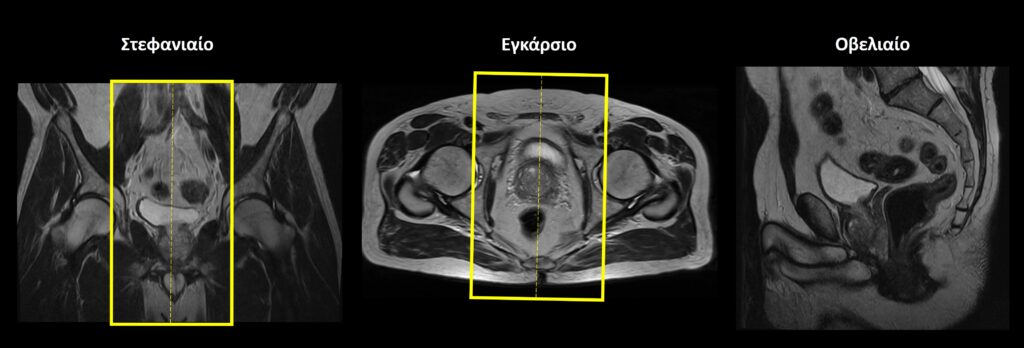

Σχεδιασμός τομών Στατικές Ακολουθίες

Οβελιαίο επίπεδο (Sagittal): οι οβελιαίες τομές σχεδιάζονται κατά μήκος των οργάνων της πυέλου τόσο στο εγκάρσιο όσο και στο στεφανιαίο επίπεδο. Η κλίση των τομών στο εγκάρσιο επίπεδο πρέπει να είναι παράλληλη με τη νοητή γραμμή που ενώνει την ηβική σύμφυση με τον πρωκτικό σωλήνα. Κατάλληλη κλίση πρέπει να δοθεί και στο στεφανιαίο επίπεδο, παράλληλα με το ορθό και τον πρωκτικό σωλήνα. Οι τομές πρέπει να περιλαμβάνουν τα όργανα της πυέλου, από την δεξιά έως την αριστερή κοτύλη.

Εγκάρσιο (Axial/Transversal): οι εγκάρσιες τομές σχεδιάζονται παράλληλα με τις κεφαλές των μηριαίων στο στεφανιαίο επίπεδο και κάθετα στονπρωκτικό σωλήνα στο οβελιαίο επίπεδο. Οι τομές πρέπει να περιλαμβάνουν τα όργανα της πυέλου, από τις λαγόνιες ακρολοφίες (πάνω) έως τον πρωκτό (κάτω).